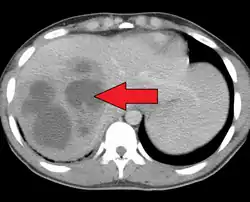

Pyogenic liver abscess

| A large pyogenic liver abscess presumed to be the result of appendicitis | |

A pyogenic liver abscess is a type of liver abscess caused by bacteria.

Diagnosis

- USG and CT scanning